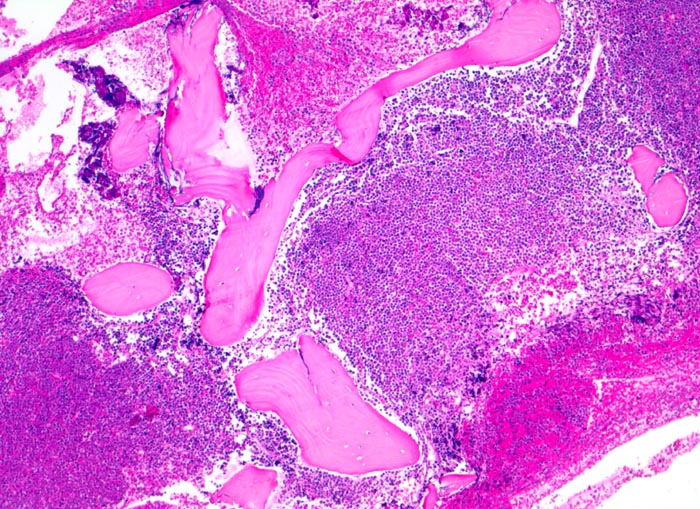

• Partielle Verdrängung des Fettmarks durch monomorphen Blastenrasen (Zellularität ca. 80%).

• Verdrängung der Myelo-, Erythro- und Megakaryopoese.

• Mittelgrosse Lymphoblasten mit wenig Zytoplasma.

• Kerne mässig polymorph, oval, teils mit Kerneinkerbungen. Feine Nukleolen. Lockeres Chromatin.

• Zahlreiche Mitosen.